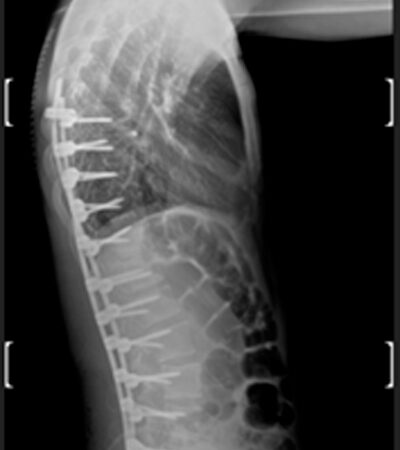

DIAGNOSI:

IPERCIFOSI DORSALE GRAVE

Radiografia dorsale pre operatoria

Intervento chirurgico eseguito:

STABILIZZAZIONE DORSO – LOMBARE CON OSTEOTOMIE CORRETTIVE

Radiografia dorsale post-operatoria